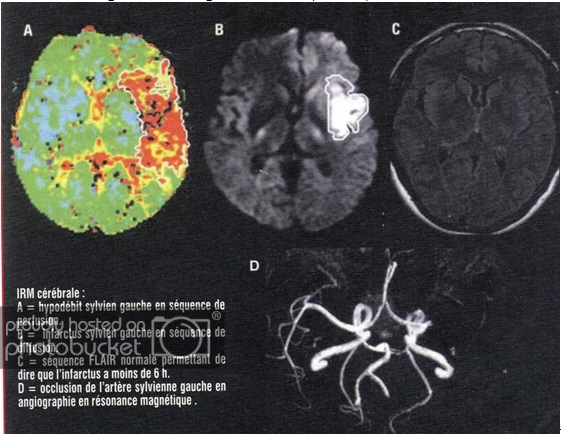

Click image for larger version

Name:	111.jpg

Views:	0

Size:	62.0 KB

ID:	1361243